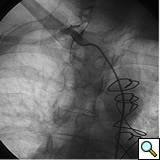

PCI of the vein and arterial grafts have unique challenges. For any PCI, guide support is very important for successful balloon and stent delivery. In a tortuous vein graft with a steep angle, advancement of a stent can be very difficult and challenging. Therefore, it is important to choose the best available catheter before starting PCI. Similar to the right coronary angiography, a JR4 guide catheter is most commonly used in this setting. However, Amplatz guide catheters for left vein grafts and multipurpose catheters for right vein grafts are better choices in certain anatomy. In Figure 8 and Figure 10 two examples of poor guide support in two vein graft interventions can be seen. Initially, a JR4 guide was used for PCI of the vein graft supplying the left anterior descending artery (LAD) without any success. However, after changing the guide to an Amplatz left 2 guide catheter, we achieved excellent support without any difficulty in advancing two stents (Figure 9). In Figure 10, difficulty is illustrated in engaging the vein graft ostium supplying the right coronary artery with a JR4 catheter. This vein graft has a very steep inferior take off from the aorta. After changing the guide to a multipurpose catheter, we were able to deliver three stents successfully without any difficulties (Figure 11). Similar challenges exist in the treatment of the left IMA or right IMA. These arterial grafts can be extremely tortuous making stent delivery very difficult. It may be necessary to use short length stents for a better deliverability or stents with lowest profile. Usually, similar to the native coronary intervention, a 6 French guide is appropriate for the routine use.

Similar to the native coronary, a 0.014 inch wire is usually used for balloon angioplasty or stenting. If the stent can not be advanced using a soft wire, the wire could be exchanged over the balloon to a stiffer wire or the second wire could be advanced and used as a body wire for a better support. If possible, filter wires or other protection devices should be used in all vein graft interventions [(Figure 2, see no-reflow chapter for details. Most commonly used work horse wires are balanced mid weight (BMW Boston Scientific), all track wire (ATW Cordis) or Prowater (Abbott Vascular)]. In the tortuous vessels, it may be necessary to exchange the wire over a balloon to a stiffer wire such as platinum plus or an iron man. Additional wire for support so called” body wire” can be utilized to improve stent delivery in tortuous vessels. Similar to the native coronary angioplasty, wire with stiffer or/and hydrophilic tips can be used for crossing a high-grade lesion such as PT choice, grand slam, PT2 wires, etc. However, these wires can easily enter a false lumen causing dissection or perforation. It is advised to exchange these wires with a softer tip wire once the lesion is crossed successfully to prevent distal vessel perforation.

One of the most common complication of PCI during vein graft interventions is the occurrence of “no-reflow.” After angioplasty or stenting of a vein graft, sudden cession of the distal flow could occur. This phenomenon thought to be secondary to distal embolization and platelet aggregation [2-4]. It can cause myocardial infarction, arrhythmias, hemodynamic collapse and death. It is usually treated with intra-coronary infusion of adenosine, calcium channel blockers, or nitroprusside [5-9]. After aggressive pharmacological treatment, it is usually reversible but it can be refractory causing severe myocardial damage and infarction. It usually occurs in old degenerative vein grafts or in thrombus containing lesions. However, based on the angiographic appearance, it is hard to predict which vessel is proned to this complication. There are few strategies developed in order to prevent this complication. Intra-venous glycoprotein IIb/IIIa inhibitors, which are very potent platelet aggregation inhibitors, despite success in the native coronary interventions have failed to decrease this complication in vein grafts PCI [10, 11]. On the other hand, distal filter devices have shown to significantly reduce the occurrence of this complication in vein grafts and should be routinely used if technically feasible [12-14]. A major limitation of distal filter devices is the absence of large distal vessels that can accommodate these devices and difficulty to advance such a bulky device across a high-grade lesion or across a tortuous vein graft. A recently approved proximal occlusion device has similar efficacy for the prevention of no-reflow in vein graft interventions [15]. By occluding the vein graft proximally during balloon angioplasty or stenting, flow can be stopped during stent expansion and atherosclerotic and thrombotic debris can be suctioned before the vein graft flow is restored preventing distal embolization. This technique requires lesions that are distal to the ostial vein graft and add substantial complexity and time to the procedure. Figure 2 shows the most commonly used protection devices for vein graft interventions.